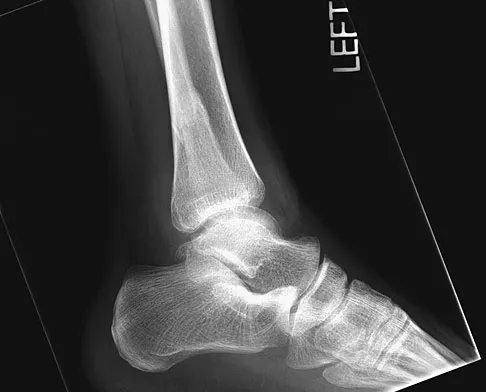

Question 67 High Yield

A 32-year-old laborer reports left ankle pain and deformity. History reveals that he sustained a left ankle fracture 2 years ago and was treated with closed reduction and casting. Radiographs are shown in Figures 25a through 25c. What is the most appropriate management?

Detailed Explanation

Corrective osteotomy of fibular malunions, with appropriate lengthening, even in the presence of early arthritis, has been shown to decrease ankle pain and increase stability. Reduction and bone grafting of the medial malleolar nonunion is also needed. There is no evidence supporting the use of intra-articular steroids or hyaluronic acid in the ankle joint. Lateral talar displacement of even 1 mm has been reproducibly shown to decrease tibiotalar contact by 40% to 42%, causing a predisposition to arthritis. Weber D, Friederich NF, Muller W: Lengthening osteotomy of the fibula for post-traumatic malunion: Indication, technique and results. Int Orthop 1998;22:149-152. Lloyd J, Elsayed S, Hariharan K, et al: Revisiting the concept of talar shift in ankle fractures. Foot Ankle Int 2006;27:793-796. Offierski CM, Graham JD, Hall JH, et al: Later revision of fibular malunion in ankle fractures. Clin Orthop Relat Res 1982;171:145-149.